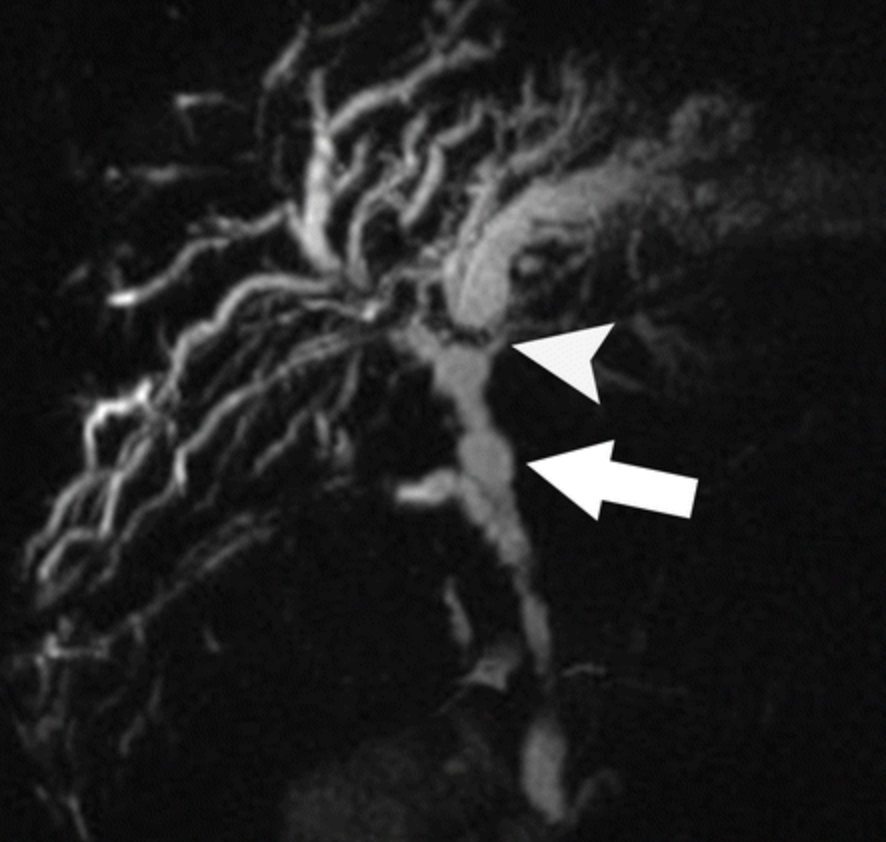

what are the locations of this disease?

- Cholangiocarcinoma

- Hilar

- originates from epithlium of main hepatic ducts or junction

- KLATSKIN TUMOUR (image)

What is this?

Two types?

- Cholangiocarcinoma

- adenocarcinoma of the biliary tree

- Two types

- scirrhous type

- worse prognosis

- Polypoid type

- scirrhous type